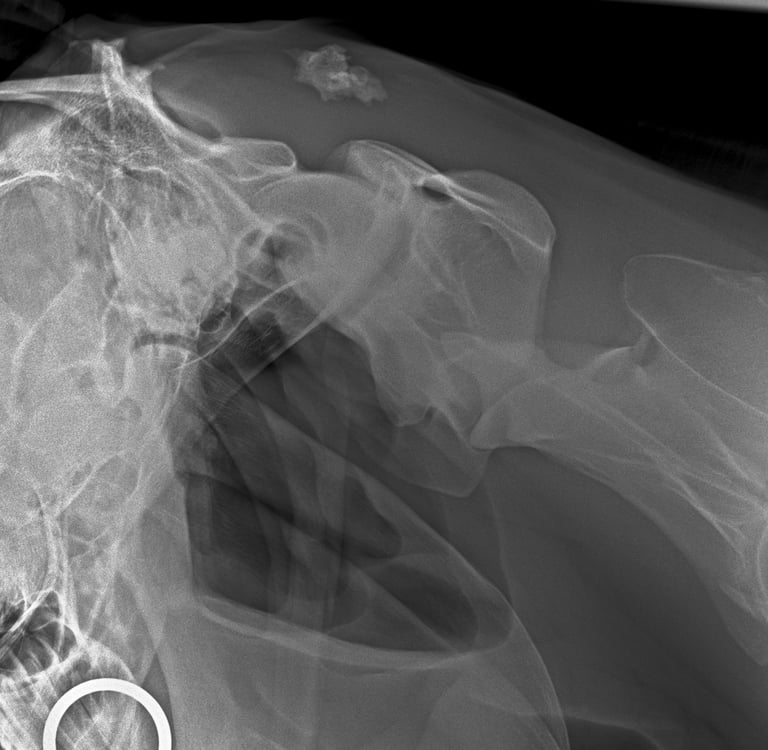

DIAGNOSTICO POR IMAGENES: ECOGRAFIA Y RADIOGRAFIA